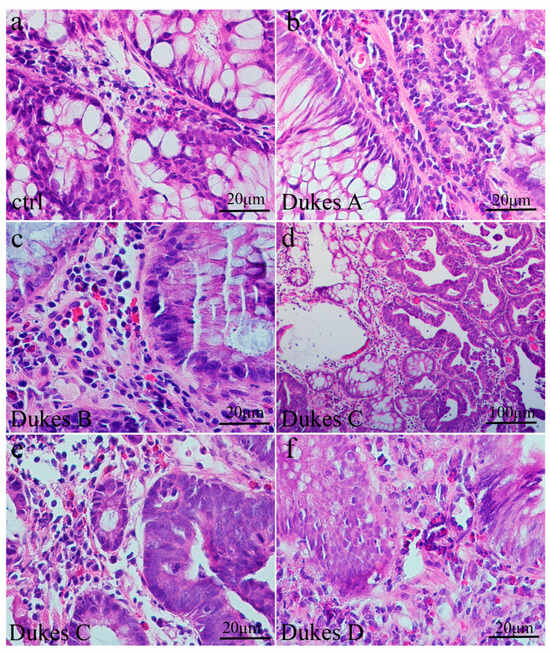

3.1. General Characteristics of CRC Visualized by Hematoxylin and Eosin Staining